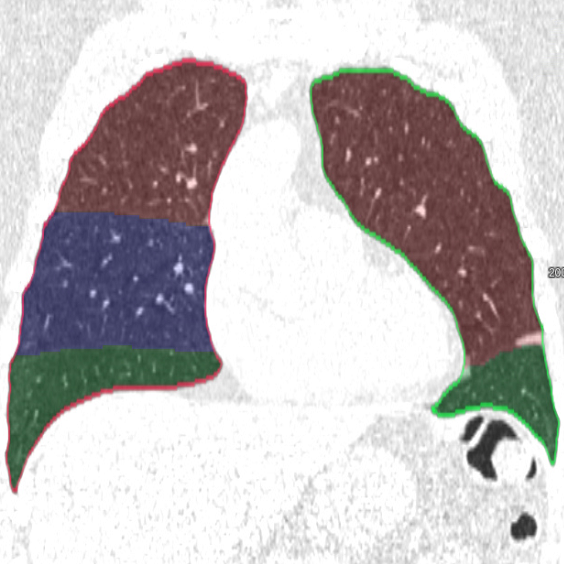

We applied the described segmentation pipeline to the 14 testing datasets which were not used for training and validation. Segmentation including postprocessing takes less than 6 seconds for a case. We compared our method to two other approaches: 1. a non-deep-learning-based automatic method [Lassen et al.(2013)Lassen, van Rikxoort, Schmidt, Kerkstra, van Ginneken, and Kuhnigk] 2. the same u-net as proposed but without weighting. The mean distance from the visible fissure improved to 1.46 mm (without weighting: 2.08 mm). See Figure 2 for plots and Figure 3 for screenshots.

We trained a 3D u-net for a lung lobe segmentation task and showed that emphasizing the lobar boundaries in the loss function improved the segmentation results (see Figure 2 and 3). The segmentation quality is comparable to the method proposed in [Lassen et al.(2013)Lassen, van Rikxoort, Schmidt, Kerkstra, van Ginneken, and Kuhnigk] and even slightly better for the left lobes. This study was performed on a small amount of data. In future work, we plan to train with the same architecture on a much larger database including a wide range of pathologies and performing an extensive evaluation with participation in the LOLA11 [LOLA11()] challenge.